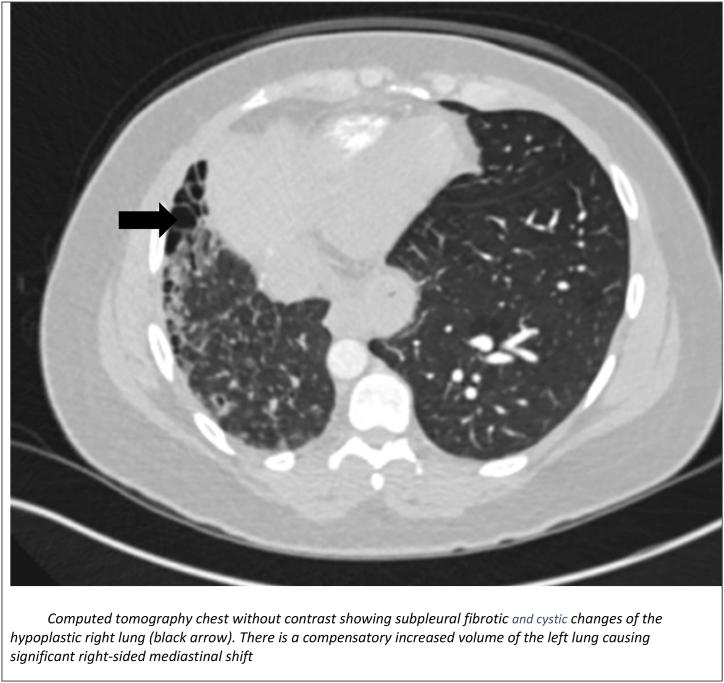

Unilateral absence of pulmonary artery (UAPA) is a congenital clinical abnormality that is rarely diagnosed in adulthood. Due to its rarity and heterogeneity as it pertains to its clinical presentation, it may be difficult to diagnose, often leading to misdiagnosis. We present a case of UAPA with unilateral pulmonary fibrosis which was misdiagnosed as rheumatoid arthritis-associated interstitial lung disease (RA-ILD). We describe the symptomology, physical examination findings, laboratory values and radiologic findings. We also describe the diagnostic challenges and approach to a patient presenting with unilateral interstitial lung disease (ILD) and highlight the importance of a comprehensive evaluation.

单侧肺动脉缺如(UAPA)是一种先天性临床异常,在成年期很少被诊断出来。由于其罕见性以及临床表现的异质性,可能难以诊断,常常导致误诊。我们报告一例伴有单侧肺纤维化的UAPA病例,该病例最初被误诊为类风湿关节炎相关间质性肺病(RA-ILD)。我们描述了症状、体格检查结果、实验室检查值和影像学检查结果。我们还描述了诊断面临的挑战以及对单侧间质性肺病(ILD)患者的诊断方法,并强调了综合评估的重要性。